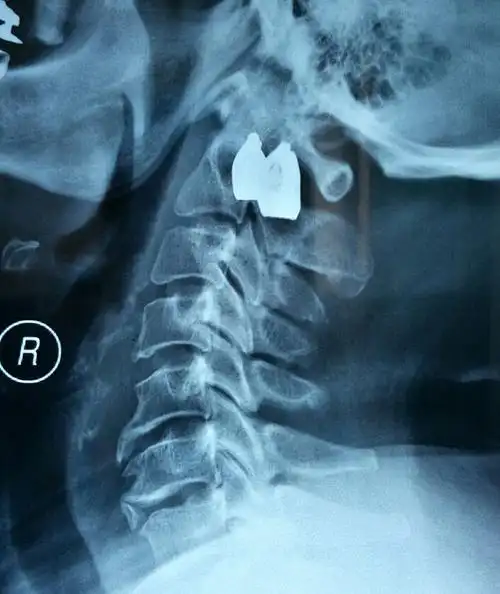

颈椎正侧位请会诊

医生说这个就是正常的颈椎侧位dr片了,叫我比较.

颈椎正侧位片

颈椎正侧位及屈伸片

颈椎前路椎体次全切髓核摘除植骨钢板内固定